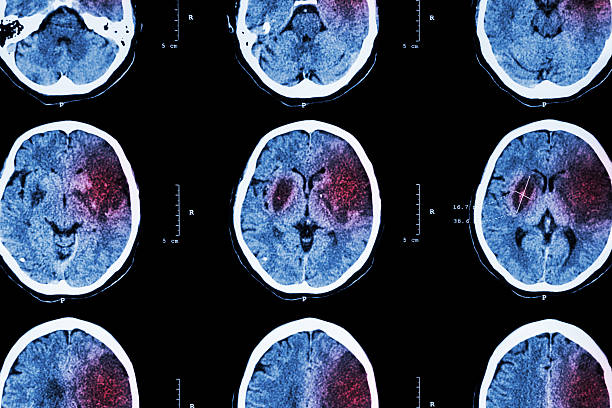

Niedokrwienie (gr. ἰσχαιμία, ischaemia, isch – ograniczenie, haema – krew) – lokalne zaburzenie ukrwienia będące skutkiem ograniczenia lub całkowitego zatrzymania dopływu krwi do tkanki lub narządu. Następstwem tego stanu jest niedostateczna podaż tlenu i składników odżywczych. W efekcie dochodzi do niedotlenienia (hipoksji), niedożywienia, a ostatecznie do martwicy tkanek dotkniętych procesem niedokrwiennym.

Przyczynami niedokrwienia jest działanie nerwów naczynioruchowych, zmiany anatomiczne zwężające lub zatykające światło tętnic np. zakrzepica, zator, ucisk oraz wstrząs prowadzący do ogólnego niedokrwienia. Następstwem niedokrwienia może być zanik narządu, zmiany zwyrodnieniowe, np. stłuszczenie, włóknienie oraz martwica.